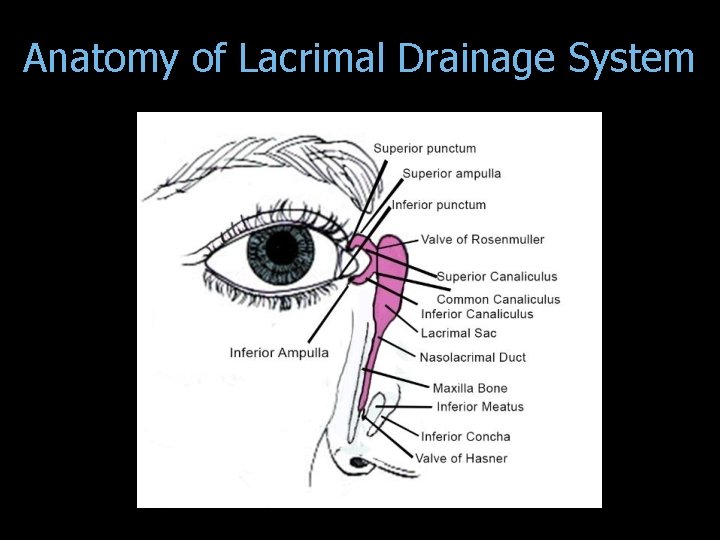

Anatomy of Lacrimal Drainage System